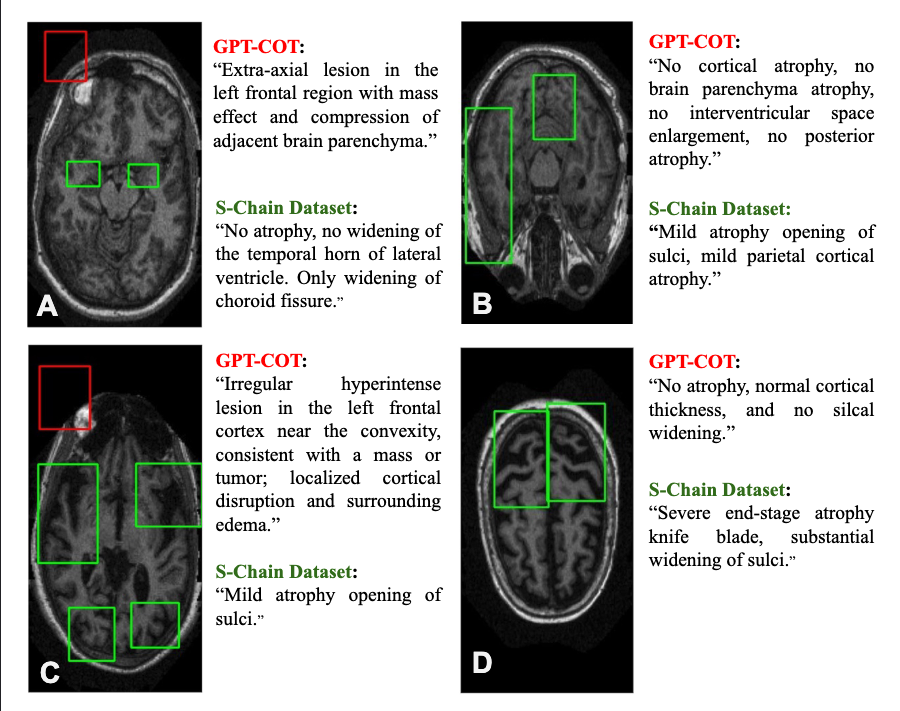

Synthetic data often suffers from hallucinations, such as incorrect or missing bounding boxes, which undermines the model's ability to ground its reasoning in visual evidence.

GPT-4.1 vs S-Chain Comparison

Comparison showing GPT-4.1 hallucination vs S-Chain ground truth

Red: GPT-4.1 hallucinates an "extra-axial lesion" that is not present. Green: The S-Chain annotation correctly identifies "no atrophy".